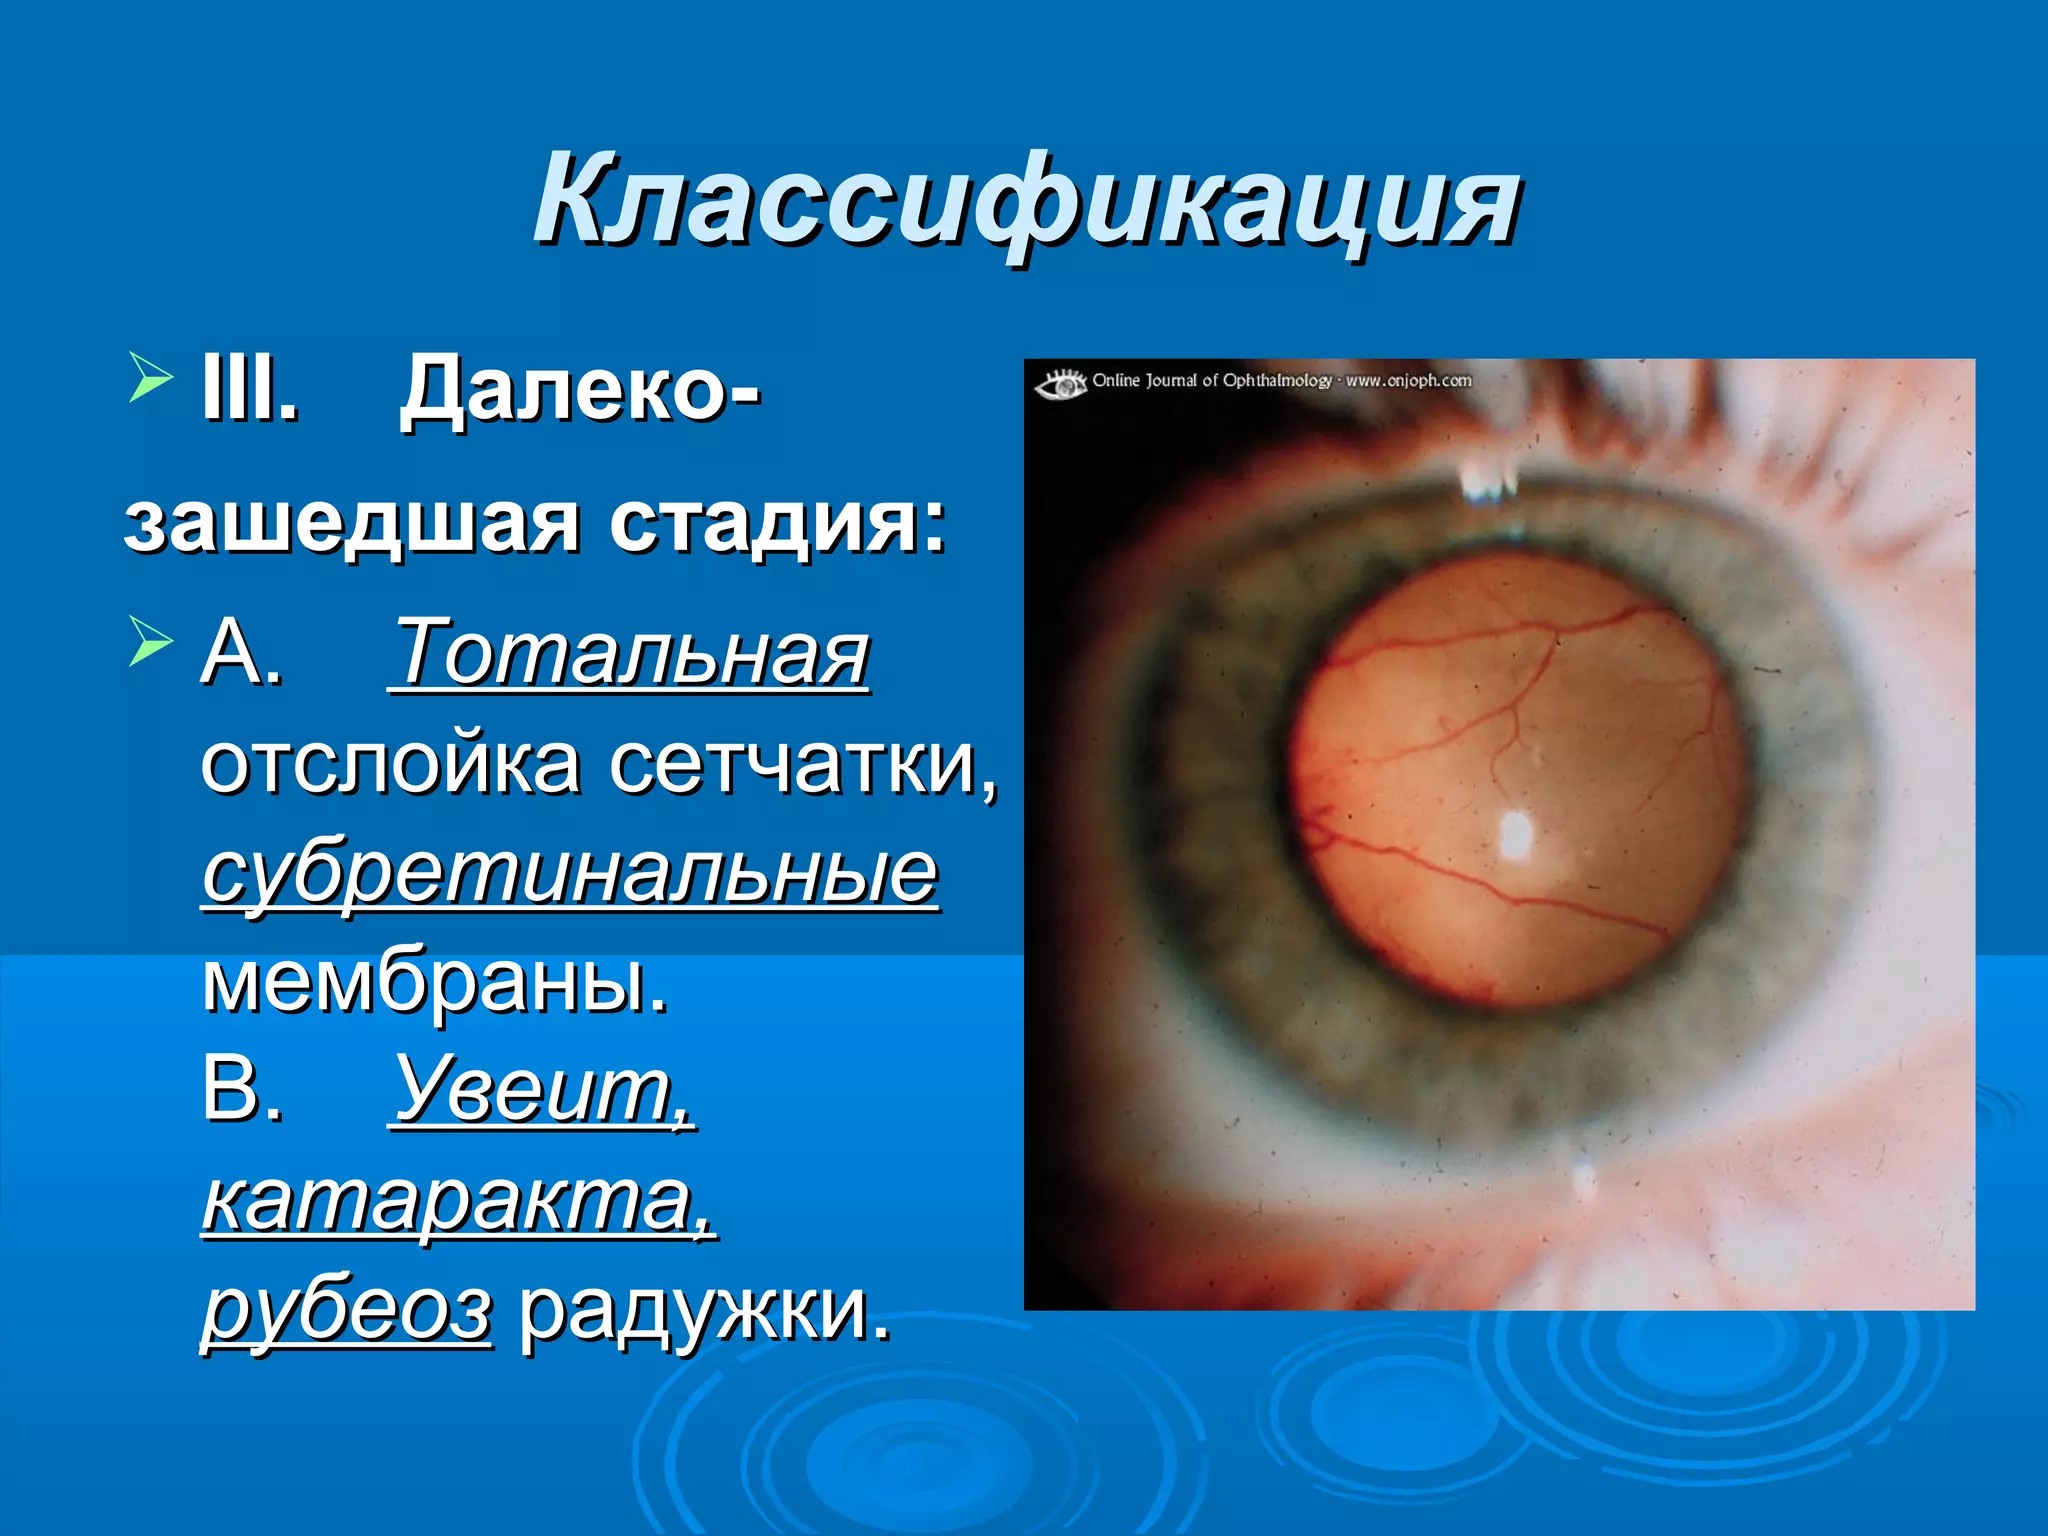

Болезнь Коатса - это идеопатическое заболевание, характеризующееся полиморфными изменениями сосудов сетчатки с массивной экссудацией, чаще всего у детей и подростков, с преобладанием среди мальчиков. Эпидемиология показывает, что заболевание проявляется, как правило, в возрасте 8-16 лет, но возможно его обнаружение и у взрослых. Основные проявления включают ретинальные аномалии, субретинальную экссудацию и постепенно прогрессирующую потерю зрения.